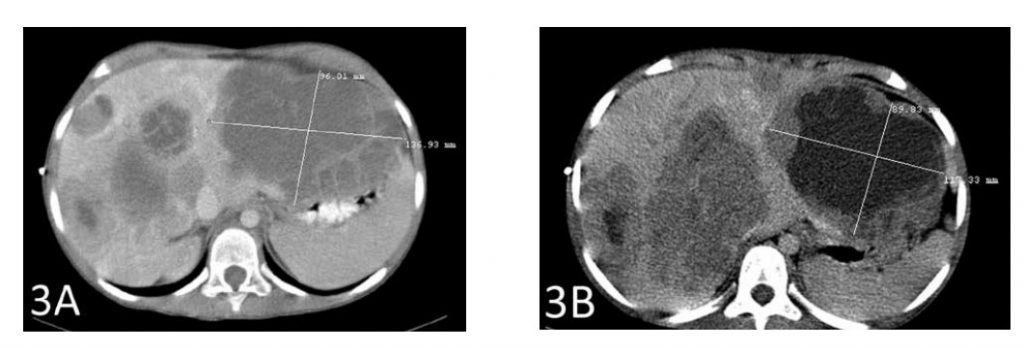

Una TC dopo un totale di 6 settimane di terapia ha mostrato una riduzione di 2 cm della metastasi epatica più grande (Figure 3A e 3B). Anche la seconda metastasi più grande si è ridotta di quasi 2 cm (Figure 4A e 4B).

La Figura 3A mostra la metastasi più grande prima dell’inizio della terapia con DCA IV. La Figura 3B mostra la riduzione di 2 cm del tumore dopo la terapia

Il caso 3 illustra la riduzione del tumore con DCA per via endovenosa in combinazione con IVC ad alte dosi. Questo risultato è stato classificato come malattia stabile secondo la definizione RECIST perché la riduzione del tumore era inferiore al 30%. Sono stati osservati effetti collaterali minimi. Sulla base delle scansioni di octreotide prima e dopo il trattamento, la riduzione delle grandi metastasi epatiche non può essere attribuita alla terapia con octreotide; nessuna delle due scansioni ha mostrato recettori di octreotide nelle metastasi epatiche. Inoltre, la scomparsa dei recettori dell’octreotide dal tumore pancreatico sottolinea ulteriormente la mancanza di benefici legati alla terapia con octreotide. Pertanto, la risposta può essere attribuita alla somministrazione di DCA, in combinazione con farmaci naturali. Con la somministrazione di DCA per via endovenosa si nota talvolta una temporanea riacutizzazione del dolore correlato al tumore, che può essere un segno della risposta del tumore con conseguente infiammazione. Un aumento improvviso della LDH sierica del paziente è coerente con questo effetto. A causa della breve durata della valutazione, non è possibile trarre conclusioni sulla durata della risposta. Gli autori hanno concluso che il DCA per via endovenosa sembra avere un’attività nell’uomo contro il carcinoma pancreatico neuroendocrino.